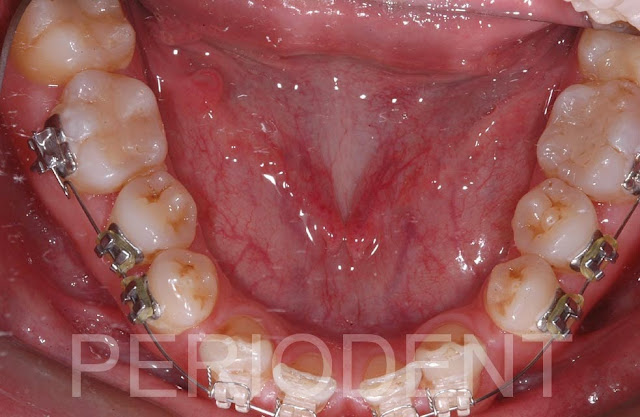

患者前下缺兩個門牙,且有牙間空隙

先請矯正醫師矯正治療調整空間集中在前下門牙區域